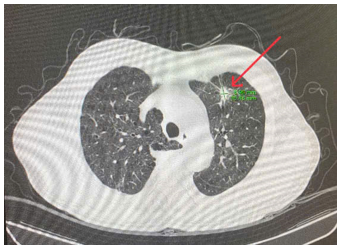

· CT lồng ngực:

Hình 6. Nốt đặc kích thước 16x10mm (nhỏ hơn phim chụp tháng 7/2024) bờ tua gai, ngấm thuốc không đồng nhất sau tiêm ở thuỳ trên phổi trái

Hình 7. Nốt đặc kích thước 9x8mm (nốt mới), bờ tua gai, ngấm thuốc 1 phần sau tiêm ở thuỳ dưới phổi phải, nhu mô còn lại có vài dải xơ xẹp phổi rải rác